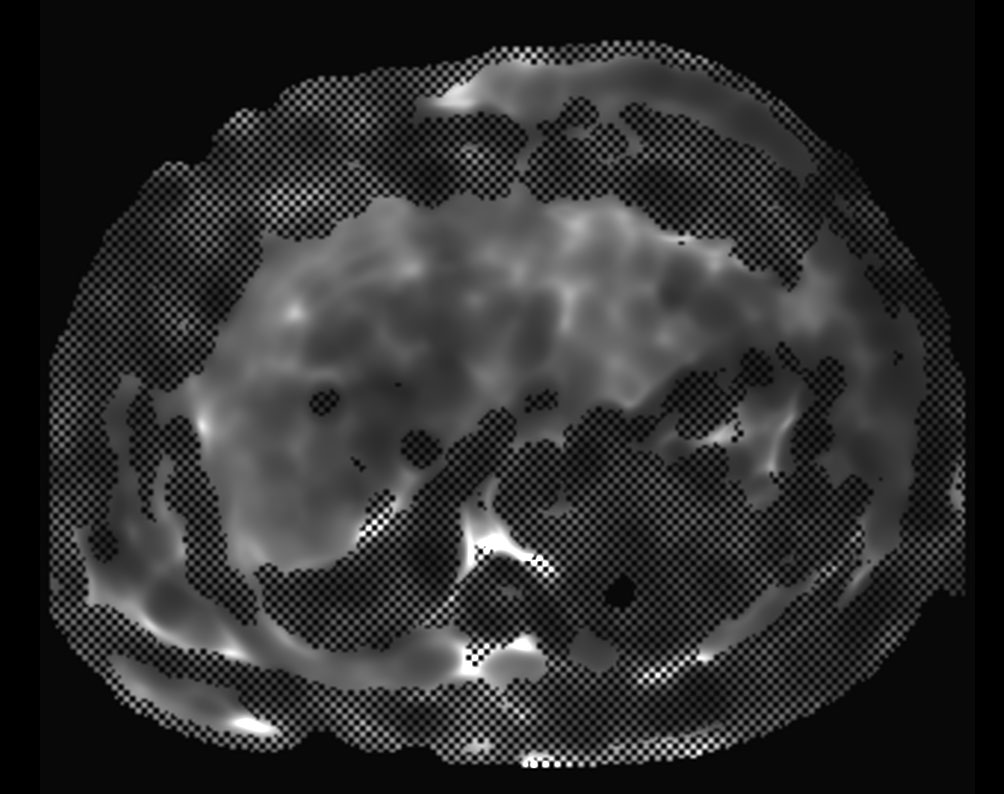

MR Elastography (confidence map) SE-EPI, 14 sec BH/8 slices

MR Elastography (stiffness map) SE-EPI, 14 sec BH/8 slices